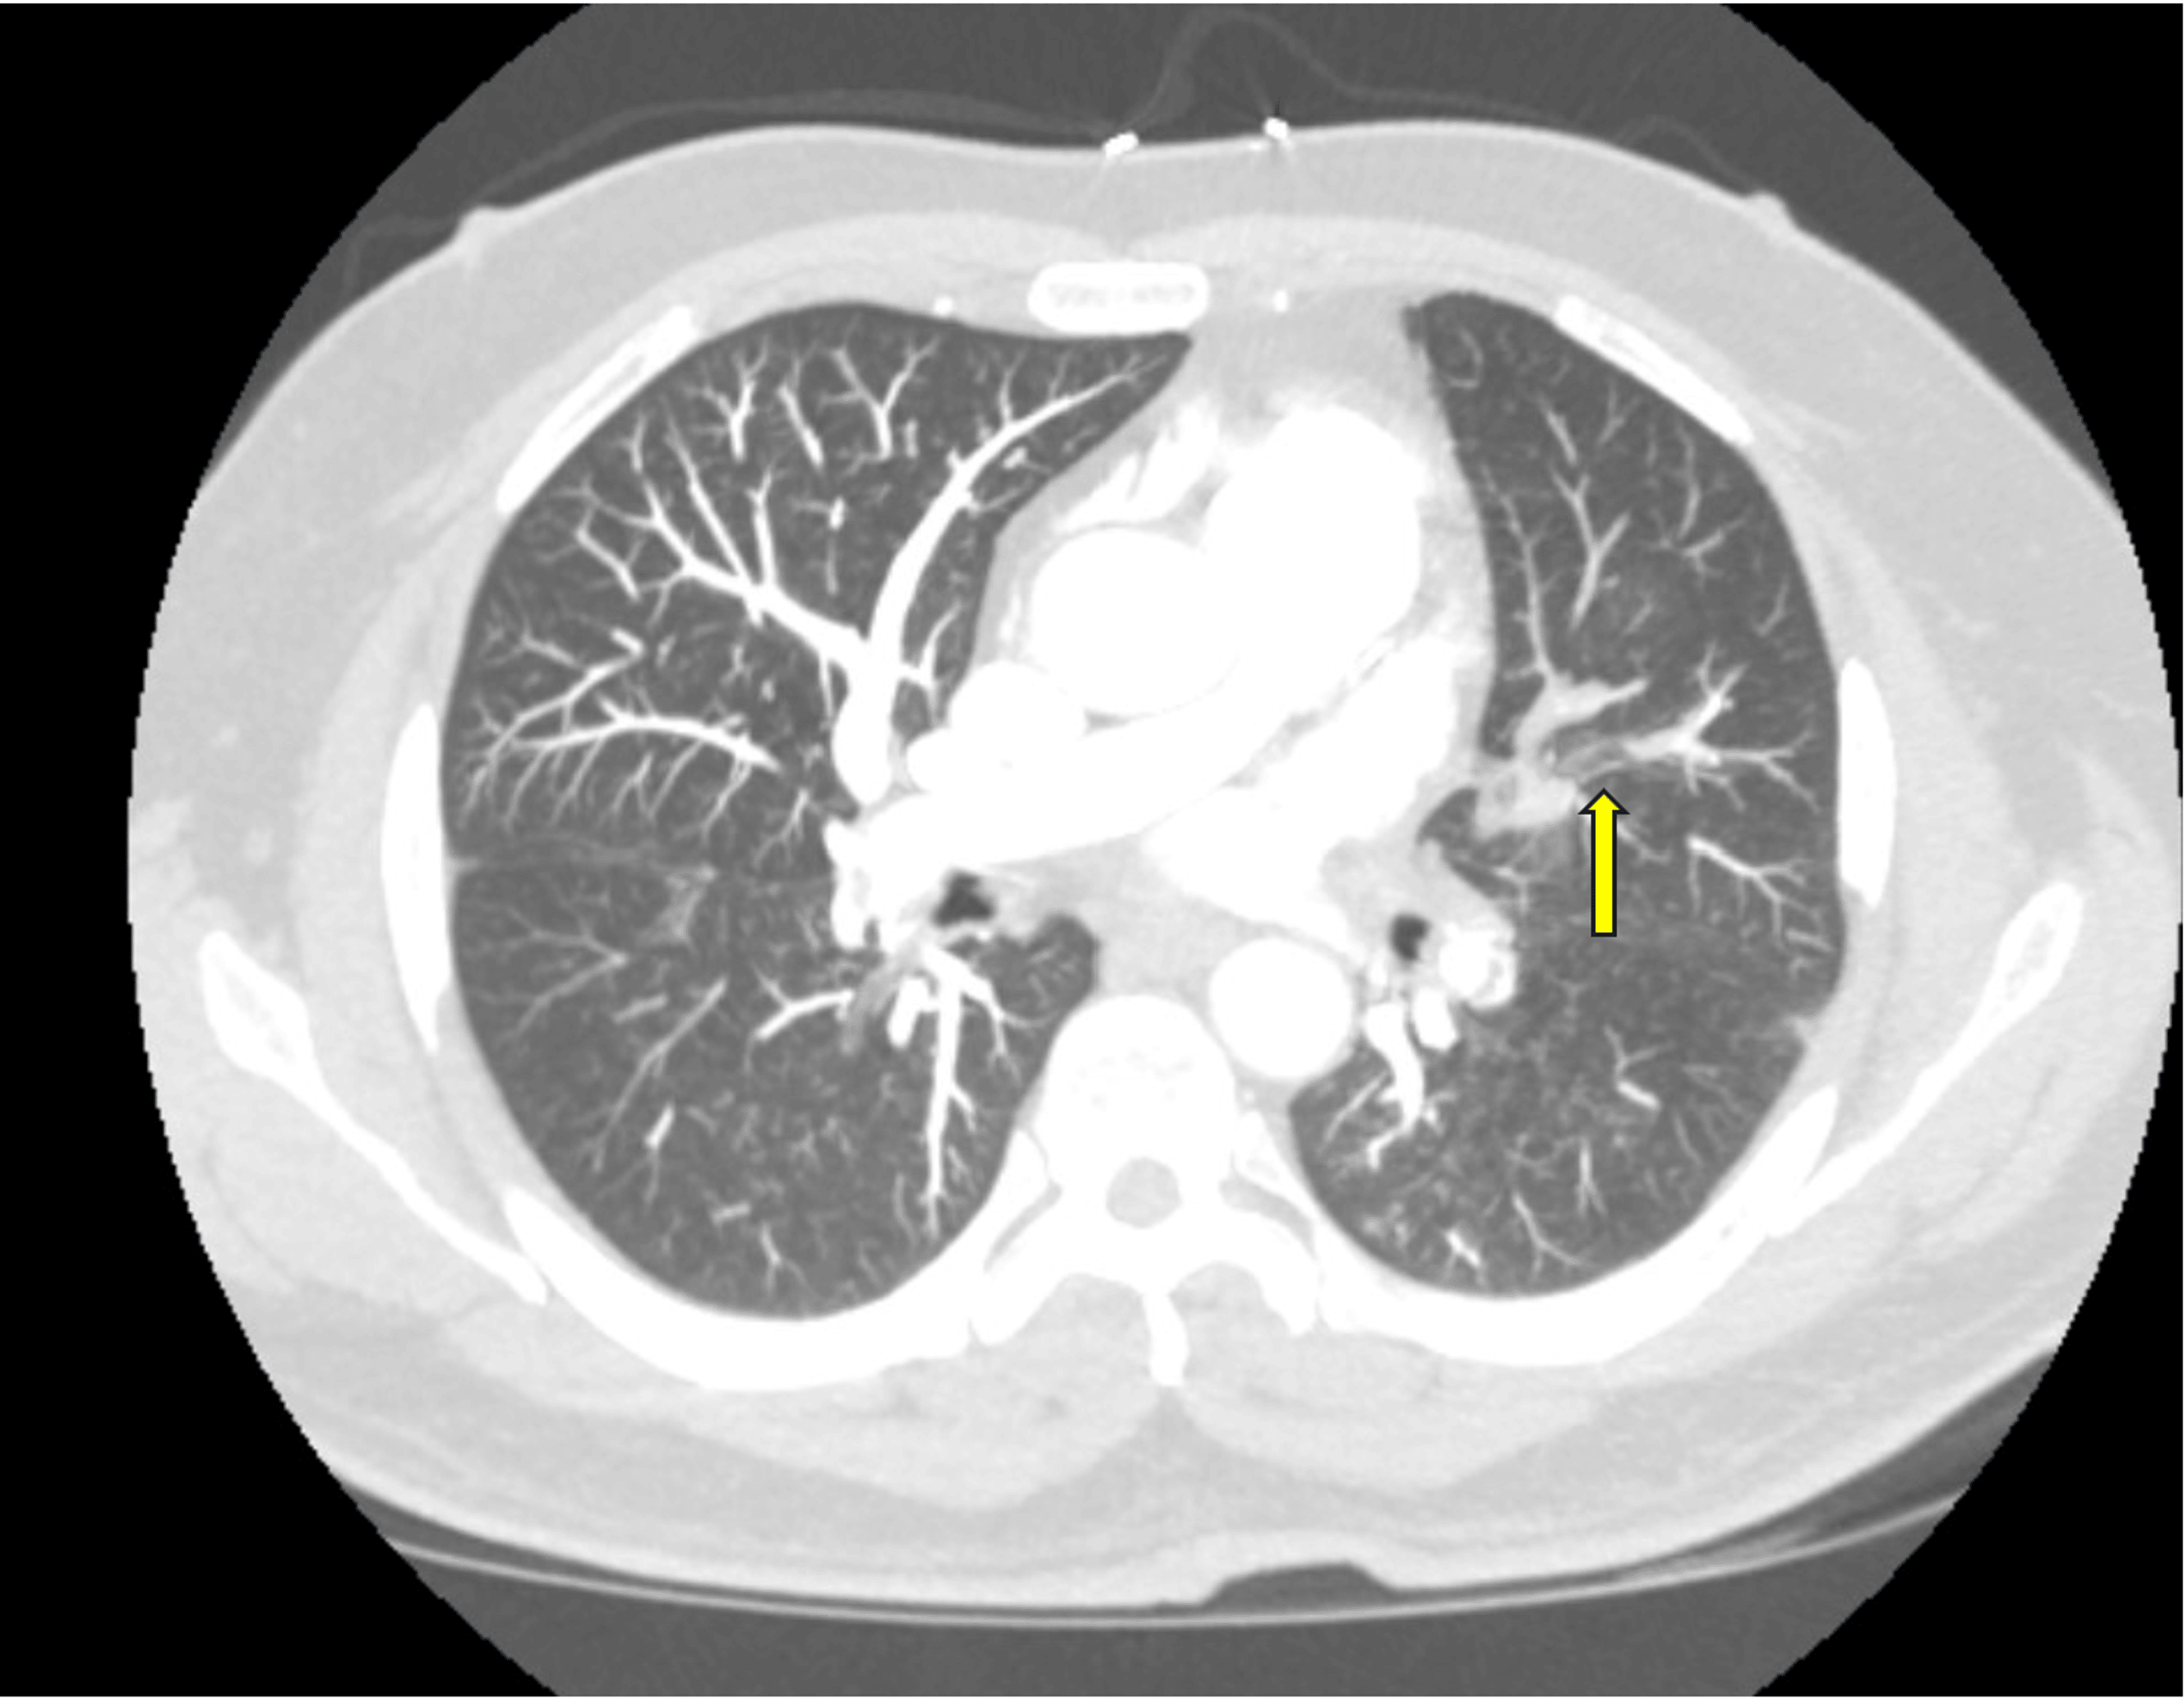

From www.semanticscholar.org

Figure 1 from Unique Case of Alpha 1Antitrypsin Deficiency Causing Protein S Deficiency Pulmonary Embolism Protein s deficiency is an inherited thrombophilia associated with an increased risk of thromboembolism. Subjects were regarded protein s deficient when protein s levels were <2.5th percentile of the controls. Conditions such as protein s deficiency, resulting from genetic mutations, are encompassed within this category of causative. Having this deficiency puts you at risk for a blood clot in your. Protein S Deficiency Pulmonary Embolism.